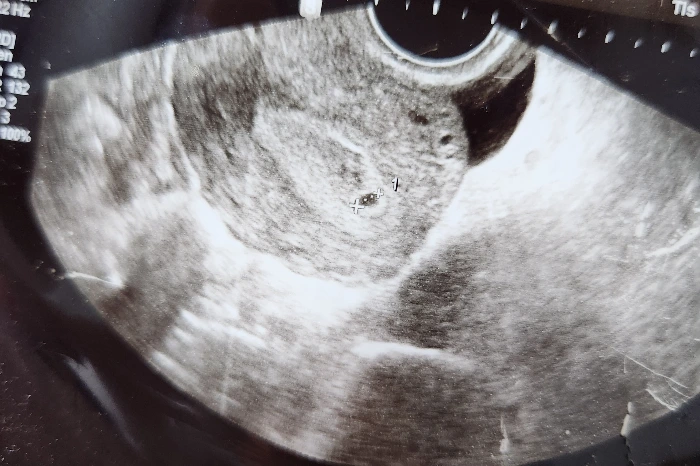

여기 아기집 보이시죠?

임신인 것 같네요.

2주 뒤에 다시 와보세요.

서른, 어느 날 덜컥 나는 엄마가 되어버렸다.